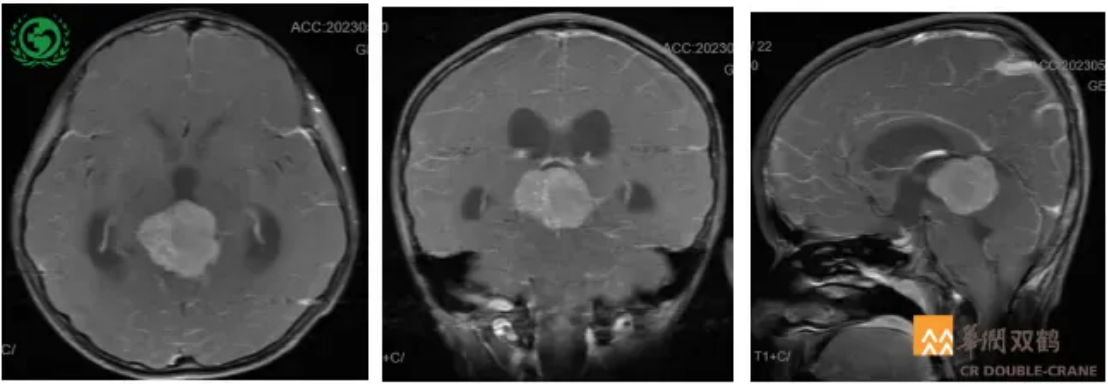

颅脑MRI+C检查提示:1.松果体区巨大占位;2.梗阻性脑积水(图1)。

图1 头部MR检查